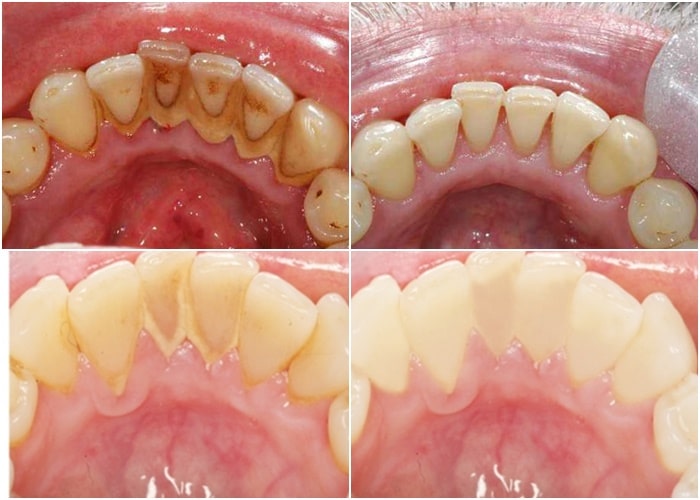

Hình ảnh cao răng bám đầy răng bệnh nhân

- Hạn chế nguy cơ mắc các bệnh lý răng miệng: cao răng là nơi trú ngụ của rất nhiều vi khuẩn có hại – chúng chính là nguyên nhân hàng đầu gây ra các bệnh lý như sâu răng, tụt lợi, viêm nha chu, mòn men răng,…

- Răng trắng sáng hơn: một trong những nguyên nhân khiến răng bị xỉn màu chính là các mảng bám cao răng. Việc loại bỏ cao răng sẽ mang lại một hàm răng sáng bóng và tăng tính thẩm mỹ cho cả khuôn mặt.